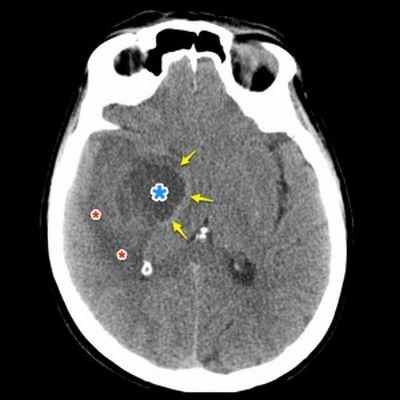

Опухоль головного мозга — глиобластома. Компьютерная томография (КТ). Синяя звездочка в центре обозначает зону центрального некроза опухоли, заполненную жидкостью. Желтые стрелки — окружающий мягкотканный компонент опухоли. Красные звездочки — перифокальный отек мозга. Наблюдается смещение срединных структур и угроза нисходящего транстенториального вклинения мозга.

Проявления опухоли на КТ-сканах без контрастного усиления включают неоднородное образование с нечеткими краями; внутренние области низкой или жидкостной плотности являются очагами некроза (представлены более, чем в 95% МФГ); внутренние области высокой плотности, являющиеся очагами геморрагии или, реже, кальцификациями (они более характерны в тех случаях, когда МФГ является результатом трансформации из астроцитомы низкой степени злокачественности); и значительный масс-эффект и отек (возогенная природа отека).

Исследование КТ с контрастным усилением значительно увеличивает выявление таких признаков, как неровные контуры образрвания, неоднородность, возможное кольцевидное контрастное усиление в периферических отделах патологической зоны.